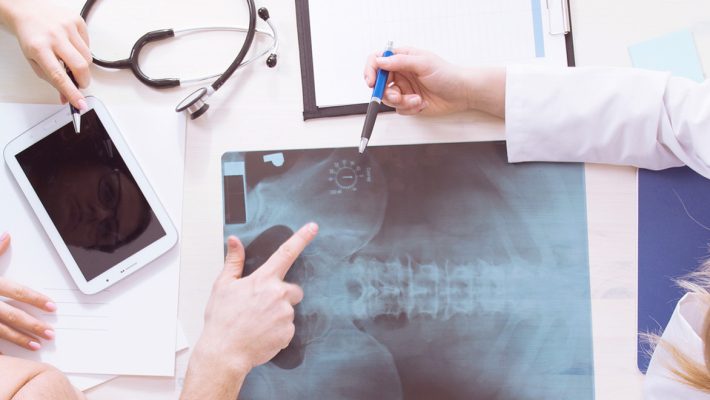

Dr. Webb’s focus is on workers’ compensation care for occupational injuries and exposures common in many industries. He provides clinical and consultation services for persons with occupational and environmental illnesses and conditions, including communicable disease prevention and control, chemical exposures and worker’s compensation cases. Services include expert clinical employee health services, pre-placement and periodic exams, medical surveillance exams and case management for workers with work-related conditions. Also offered are comprehensive independent medical evaluations and medical review officer (MRO) services. His experience and training make him an expert in occupational medicine, independent medical examinations (IMEs), disability and impairment ratings, and workers compensation care.